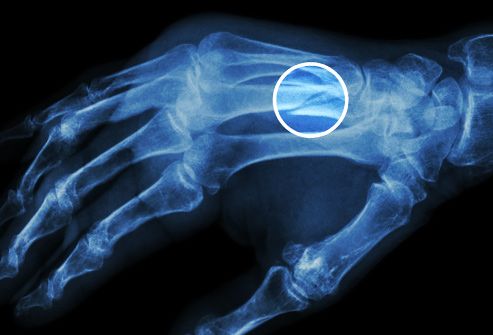

12. Bệnh Gout

Tình trạng này biểu hiện như một cơn đau và sưng đột ngột ở một trong các khớp của bạn, thường là ngón chân cái. Đây là một dạng viêm khớp do sự tích tụ của axit uric trong cơ thể bạn. Nếu bạn dùng một số loại thuốc điều trị huyết áp cao, ăn thịt đỏ và động vật có vỏ hoặc uống rượu, bạn sẽ có nguy cơ mắc bệnh cao hơn. Chất tạo ngọt trong soda có tên là fructose cũng làm tăng nguy cơ mắc bệnh và béo phì cũng vậy.